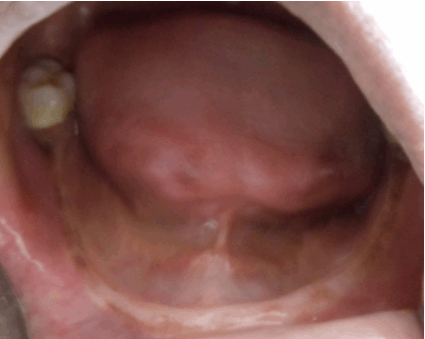

Physical examination revealed symmetrical, well demarcated, yellow keratotic plaques on the skin of the palms and soles, which extended to the dorsal surface of the finger joints and also over the dorsal surface of the feet. These keratotic plaques on the skin were dry, scaly and rough on palpation (Figure 1). On intra-oral examination, it was found that except for the canine and the erupting lower third molar, all the other permanent tooth including the left lower canine were missing. (Figure 2). Mobility was present in all permanent canines that were present. The gingiva in relation to the existing permanent tooth was red, edematous with marked clinical attachment loss. Despite the severity of the periodontal involvement, no visible local factors were found. The mucosa of the edentulous area near the periodontally involved teeth was normal. The dental panoramic radiograph showed severe alveolar bone loss in relation to the existing permanent teeth up to the apical third of the roots, giving the teeth a 'floating in air' appearance (Figure 3). The lateral view of the skull radiograph showed no evidence of intracranial calcification. Since the prognosis was very poor for the remaining permanent teeth, complete extraction of the mobile teeth, with subsequent prosthetic rehabilitation was advised.

Figure 3: The dental radiograph showing severe alveolar bone loss giving the teeth "floating in air" appearance in the male patient (case 1).